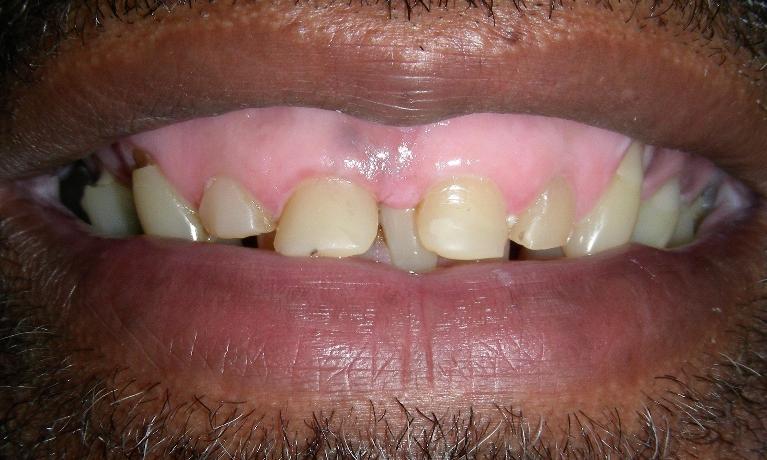

Before

Laminate composite resin veneers

This patient came to our office with severely eroded enamel. This condition can result from excessive use of acidic foods (such as lemons or soda), or other causes.

When the enamel is not present to protect the teeth, the softer dentin underneath is far more vulnerable to further destruction.

This case was restored with composite resin veneers, and was completed in one session. In cases such as this, little or no drilling of the natural tooth structure is necessary.